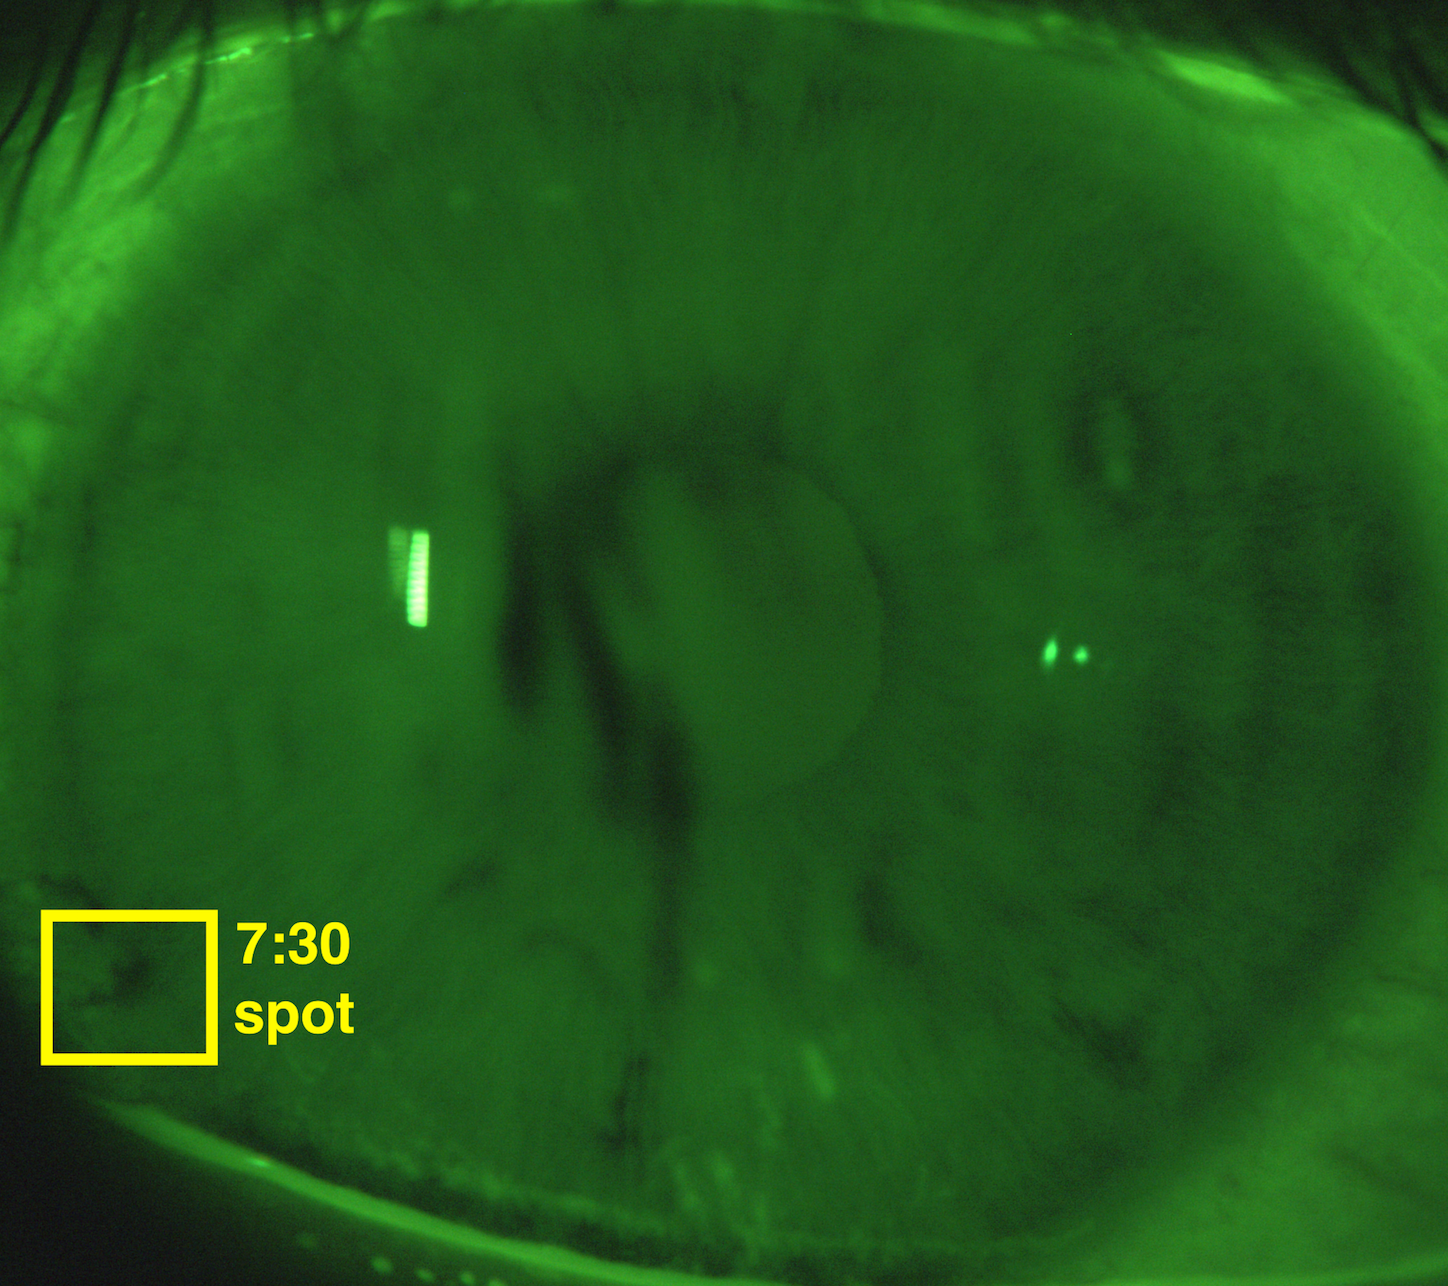

Marangoni effect-dominated thinning is characterized by strong, outward flow and small evaporation rates. Figure 4 shows the fit to the S10v1t6 12:30 spot as an example; the data for the fit is shown in Figure 3.

The S10v1t6 12:30 spot is a distinctive breakup instance because it is partially hidden by eyelashes and develops very quickly in the later half of the trial, as seen in Figure 3b. We fit this instance with two ghost time levels for several reasons. Once the eyelash and lid move so the location where FT-TBU forms is visible, there is already substantial decrease in the measured FL intensity in the center of breakup–a 50% difference as compared to the edges of the breakup region. If we compare this to the S18v2t4 7:30 spot, which we choose to fit with a single ghost time level, the latter shows only a 20% difference between the measured FL intensity at the center of breakup and at the edges of the breakup region (see Figure 2 of Online Resource 1). Secondly, fitting the S10v1t6 12:30 spot instance with a single ghost time level results in a 21% increase in the residual, indicating a significantly worse fit.

Refer to caption

(a)

(b)

(c)

Figure 3: Extracted data for the S10v1t6 12:30 spot. In (c) the image has been brightened and contrast-enhanced.